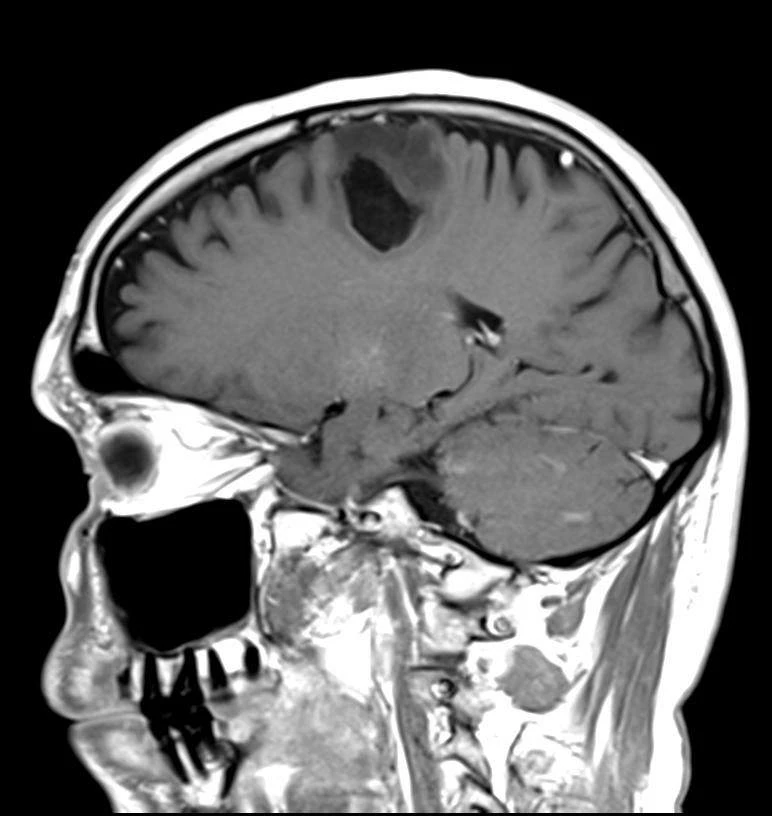

Семь менингиом и метастаз (рака молочной железы).

Четко видно, как по строению отличаются доброкачественные опухоли от злокачественных.

Первые яркие, четкие, шаровидные/полушаровидные, видно прикрепление широким основанием к костям, даже у самой мелкой.

А метастаз неровный, неяркий, нечеткий, неровный, из-за некроза, инвазии в мозг и перифокального отека.

Смотрим и запоминаем!